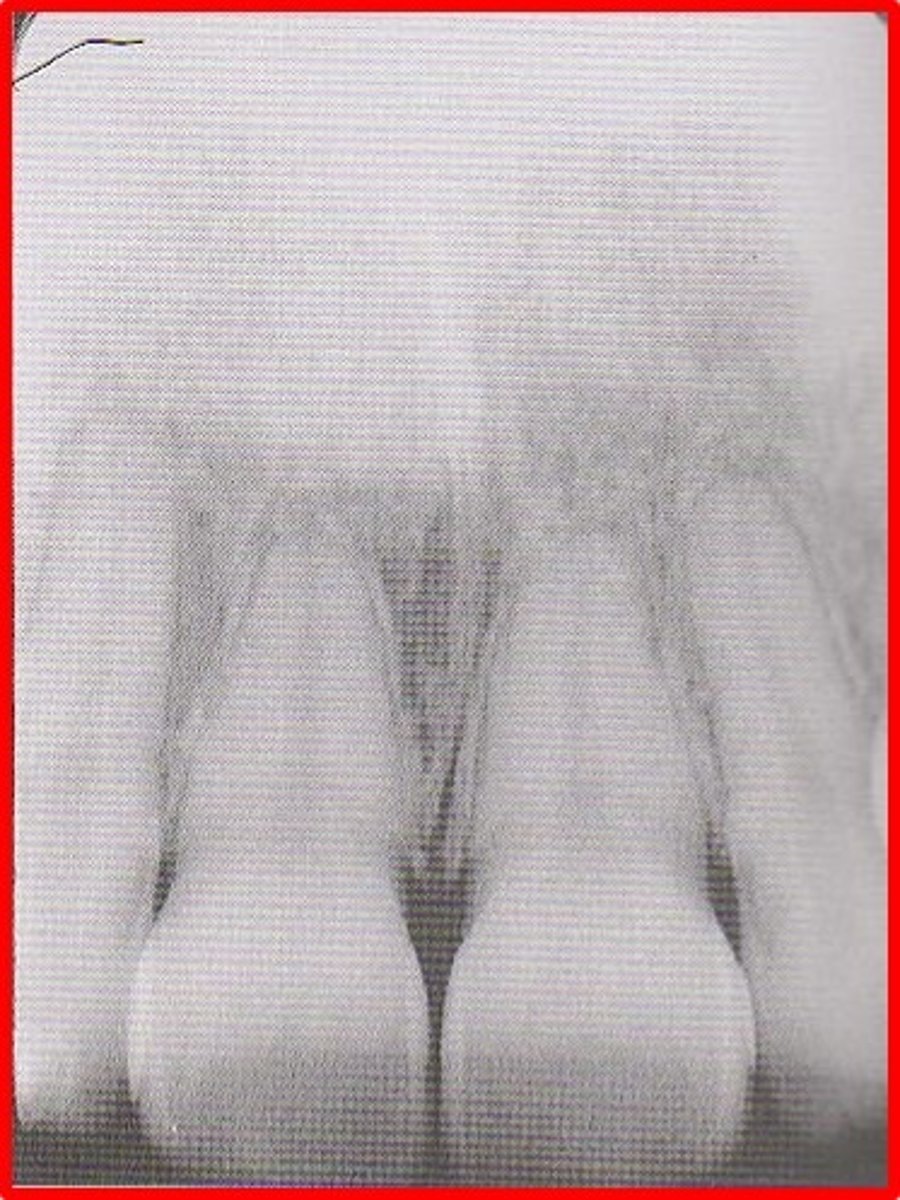

median suture

"crack" between roots of maxillary central incisors

area of incomplete fusion

radiolucent

incisive foramen

hole in the bone of the maxilla and between roots of incisors